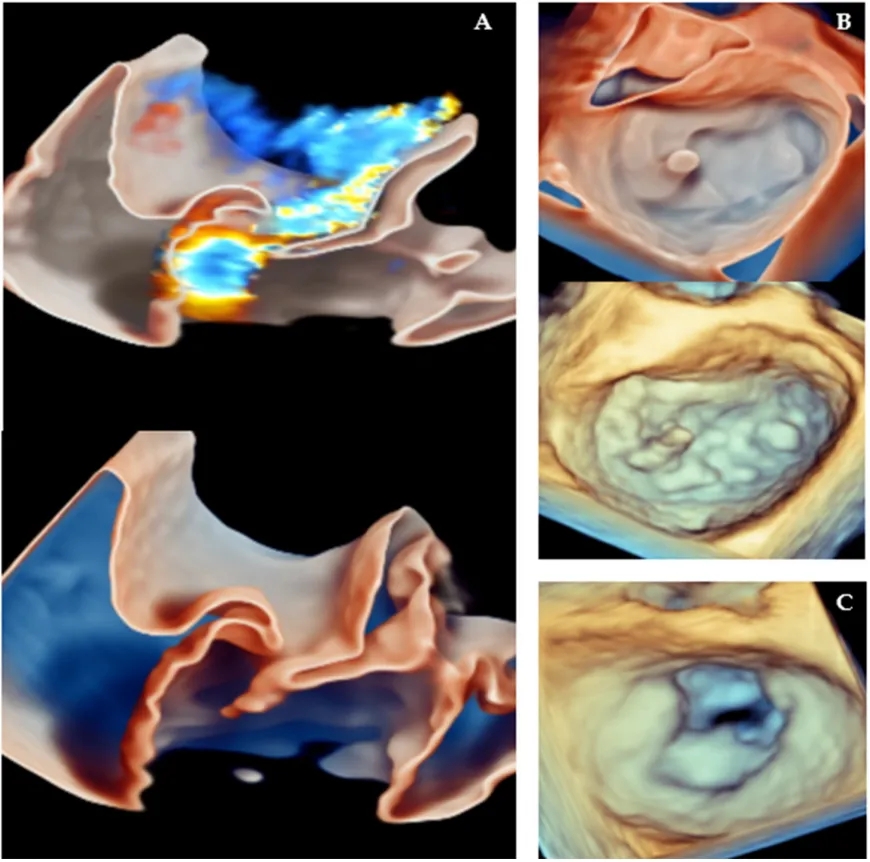

传统上,二维成像一直是评估二尖瓣装置、识别二尖瓣反流机制、预测二尖瓣修复术后并发症的基石;然而,二维成像在空间定位、深度感知方面存在局限性,且需要对二尖瓣复杂的三维结构进行心理重建,这可能会降低诊断准确性和可信度。三维经食管超声心动图提供了二尖瓣的实时正面视图(图6),增强了外科医生识别脱垂、连枷或裂隙病变的能力,尤其是在复杂的双叶或交界区疾病中。

图6.导致二尖瓣反流的二尖瓣病变的三维经食管超声心动图表现:(A)使用玻璃渲染模式显示的二尖瓣后叶连枷,分别为带三维彩色(上方)和不带三维彩色(下方);(B)二尖瓣的“正面” 视图,显示二尖瓣后叶P1扇叶小部分的连枷,分别为带玻璃渲染模式(上方)和不带玻璃渲染模式(下方);(C)二尖瓣反流患者风湿性二尖瓣的“正面”视图(本例中二尖瓣修复术不可行)。